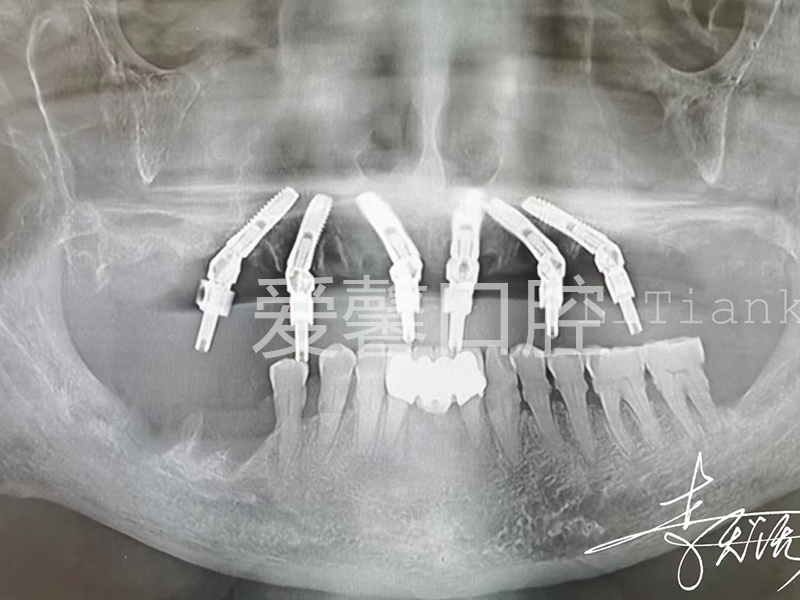

案例展示